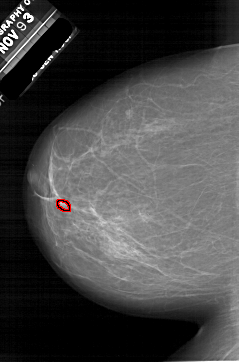

A_1952_1.LEFT_CC

LEFT_CC LINES 6151 PIXELS_PER_LINE 4051 BITS_PER_PIXEL 12 RESOLUTION 43.5 OVERLAY

FILE: A_1952_1.LEFT_CC.OVERLAY

TOTAL_ABNORMALITIES 1

ABNORMALITY 1

LESION_TYPE CALCIFICATION TYPE PLEOMORPHIC DISTRIBUTION CLUSTERED

ASSESSMENT 4

SUBTLETY 2

PATHOLOGY BENIGN

TOTAL_OUTLINES 1

BOUNDARY